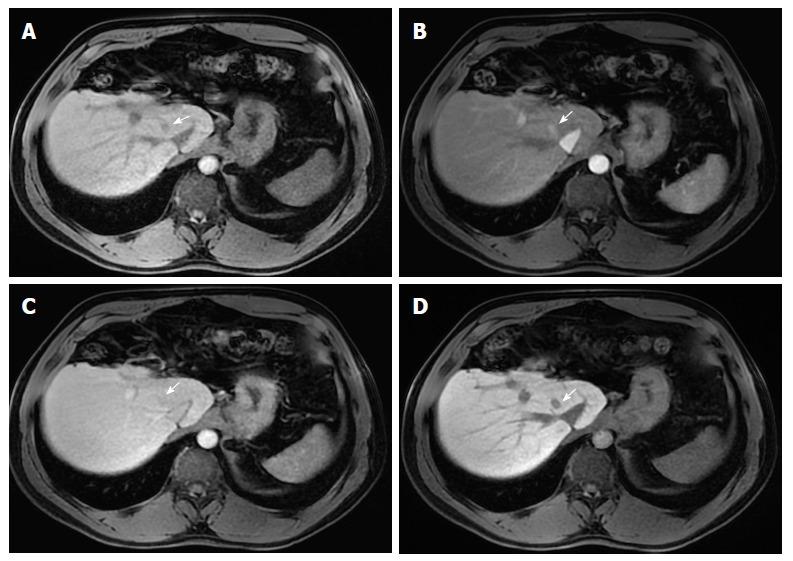

Hepatocellular carcinoma (HCC) usually develops in the setting of chronic liver disease. In the adequate clinical context, both multiphasic contrast-enhanced CT and magnetic resonance imaging are non-invasive modalities that allow accurate diagnosis and staging of HCC, although the latter demonstrates greater sensitivity and specificity. Imaging criteria for HCC diagnosis rely on hemodynamic features such as hyperenhancement in the arterial phase and washout in the portal or equilibrium phase. However, imaging performance drops considerably for small (< 20 mm) nodules because their tendency to exhibit atypical enhancement patterns. In order to improve accuracy in the diagnosis and staging of HCC, particularly in cases of atypical nodules, ancillary features, ., imaging characteristics that modify the likelihood of HCC, have been described and incorporated into clinical reports, especially in Liver Imaging Reporting and Data System. In this paper, ancillary imaging features will be reviewed and illustrated.

肝细胞癌(HCC)通常在慢性肝病背景下发生。在适当的临床背景下,多期对比增强CT和磁共振成像都是非侵入性检查方法,可实现HCC的准确诊断和分期,尽管后者具有更高的敏感性和特异性。HCC诊断的影像学标准依赖于血流动力学特征,如动脉期强化和门脉期或平衡期廓清。然而,对于小(<20mm)结节,其成像表现会显著下降,因为它们倾向于表现出非典型强化模式。为提高HCC诊断和分期的准确性,特别是非典型结节病例,已描述了辅助特征,即改变HCC可能性的影像学特征,并将其纳入临床报告,尤其是肝脏影像报告和数据系统。本文将对辅助影像学特征进行综述和说明。